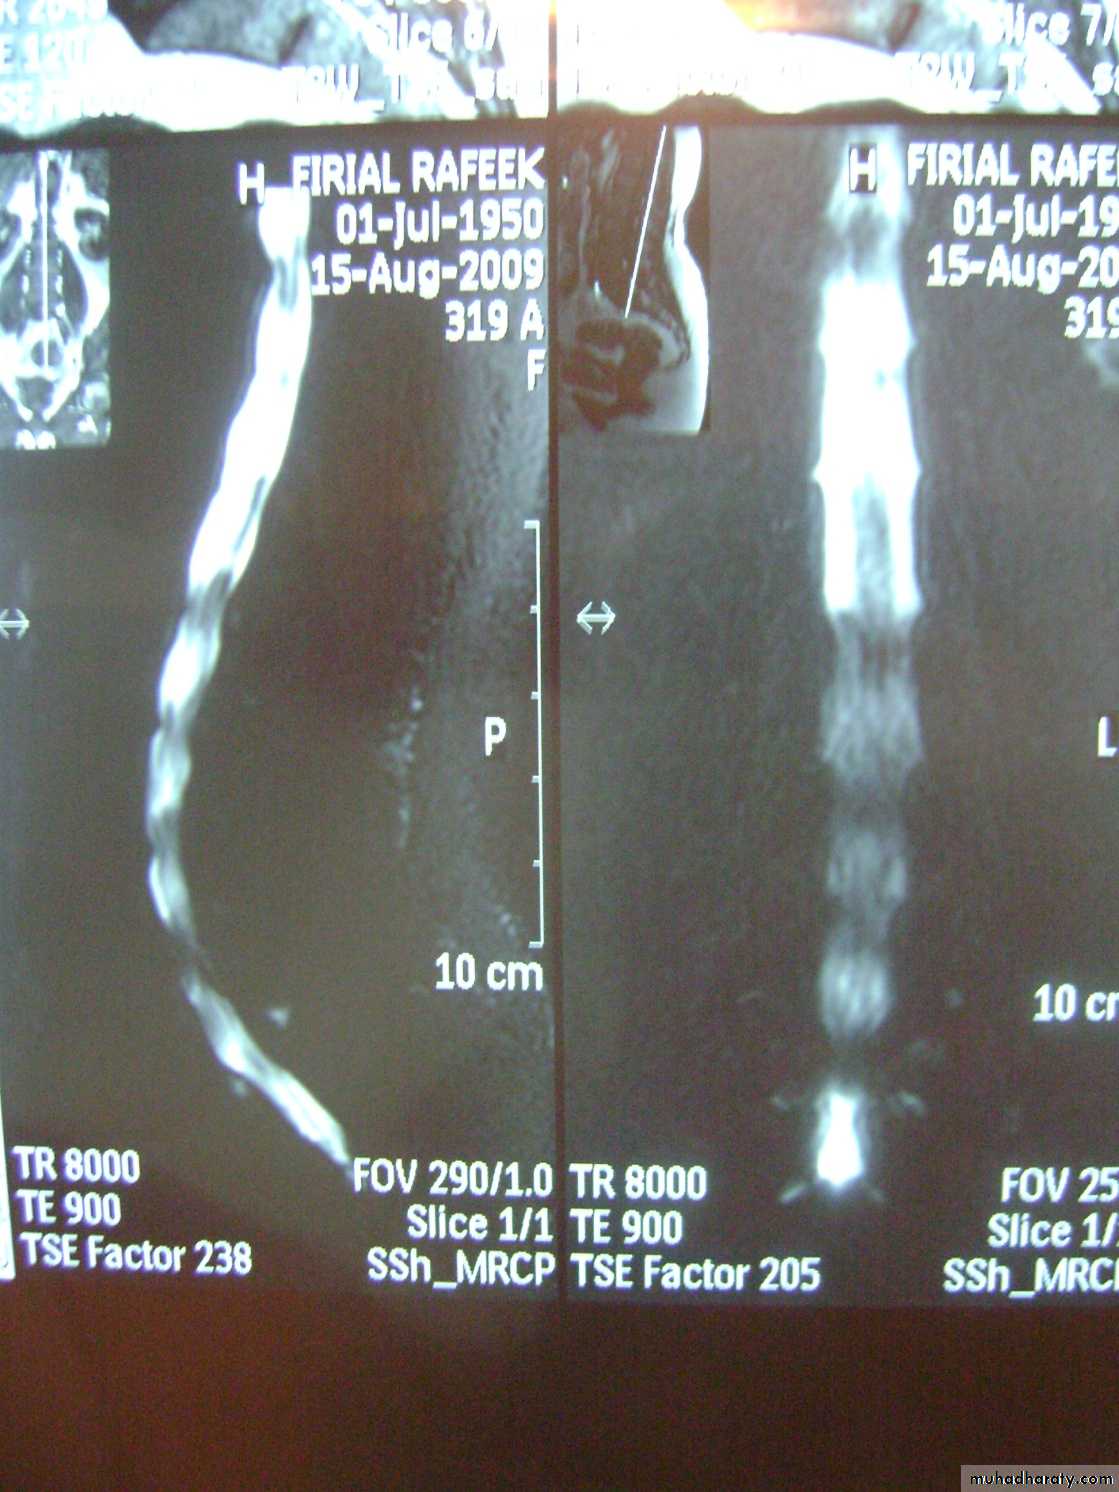

MR imaging